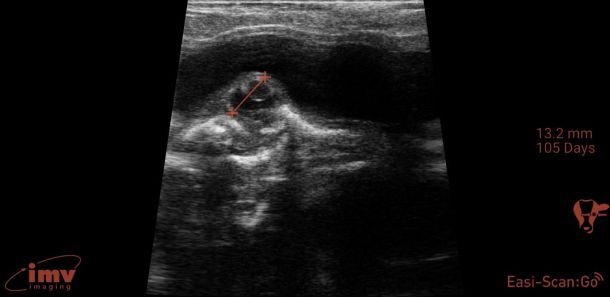

Ageing and foetal assessment

Detailed ultrasonography can detect pregnancy from 22-24 days post-insemination but due to higher rates of loss and inconsistency in quickly detecting the foetus, it is advisable that ultrasonographic pregnancy diagnosis at 28-30 days post-insemination is performed as it becomes very reliable (see Photo 2)2. At this point, the embryo becomes visible as a small, echogenic (white) structure suspended within the black (anechoic) uterine fluid2. Beyond this point, ageing is performed by either measuring or ‘eyeballing’ foetal crown-rump length, head or trunk diameter, head length or eyeball diameter (for references lengths see Table 1)6,7. Modern ultrasound machines will automatically give an estimated days in-calf, if the image is frozen and a distance is measured, but the author finds that the grid function (where a box represents 10mm) is a more useful way to eyeball these measurements without having to freeze the image. Thus thinking in boxes allows the user to reliably age using the crown rump length up to day 60 and then using head diameter and/or eyeball from days 60-150 days (see Photo 3). Measuring the placentomes is not a very reliable method to accurately age owing to the fact that placentome size will vary depending on where in the horn it is located, with smaller placentome being at the edge of the horns2.

Foetal heartbeat can be used to assess foetal viability and it is detectable from early pregnancy examination (i.e., 28 days onwards)2. Not many practitioners will measure the rate but will, rather, check for presence/absence to assess foetal viability. If heart rate is measured, it is typically 160 to 200 beats per minute (bpm) in early gestation and this can reduce to closer to 100-120bpm in later gestation. Other things that can be assessed for viability are: foetal movement, the appearance of allantoic and amniotic fluid and foetal morphology. Lack of foetal movement, abnormal cloudy fluid, and abnormal foetal appearance for the stage of gestation, are signs the pregnancy is being resorbed or lost or deformed2.